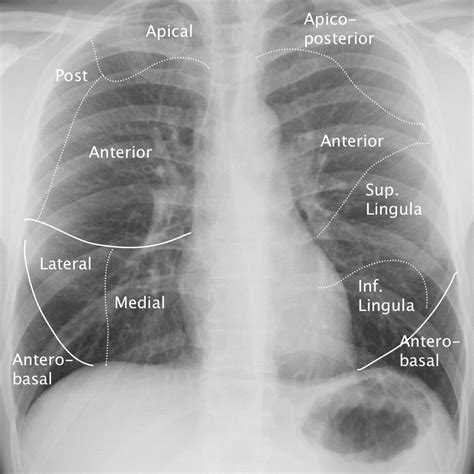

The lingula is a small, tongue-shaped lobe located in the left lung. It is part of the upper lobe of the left lung and is situated in the anterior and superior segments. The lingula is unique to the left lung and is not present in the right lung. This anatomical difference is due to the presence of the heart, which shifts the left lung slightly to accommodate its position.

The lingula is further divided into two segments:

• Superior segment of the lingula: This segment is located above the inferior segment and is responsible for a portion of the upper lobe's function.

• Inferior segment of the lingula: This segment is located below the superior segment and contributes to the lower part of the upper lobe's function.